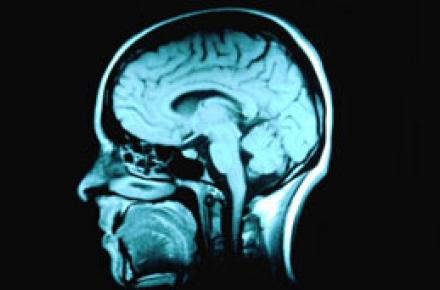

• اختلالات در بافت سفید مغز معتادان به اینترنت

اختلالات در بافت سفید مغز معتادان به اینترنت